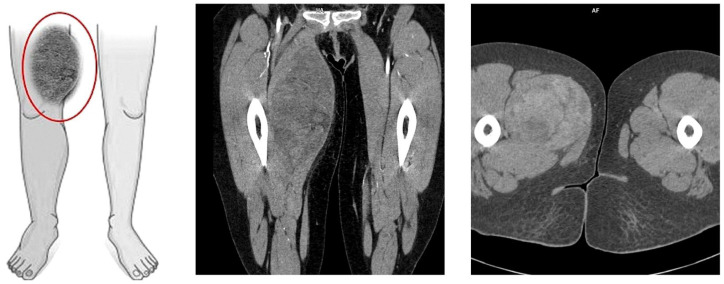

Case presentation: We report the case of a 36-year-old female patient on the 11th day of the puerperium after a cesarean section. The patient presented to the gynecology ward owing to the sudden appearance of a tumor in the medial part of her right thigh. The lesion was non-painful, mobile, soft, approximately 20 cm in diameter, and protruded above the level of the rest of the thigh surface. A suspicion of hematoma was raised. The final diagnosis was high-grade MLPS.